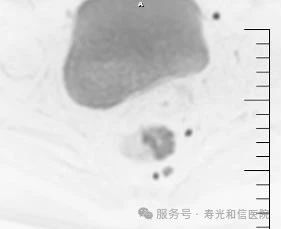

(直肠癌病人周围淋巴结转移)